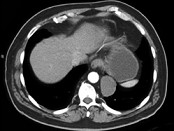

- 单项选择题男,33岁, 背部不适,无发热, 结合CT图像,选择最可能的诊断是 ( )

A、椎旁脓肿

B、神经源性肿瘤

C、脑脊膜膨出

D、食管囊肿

E、淋巴瘤